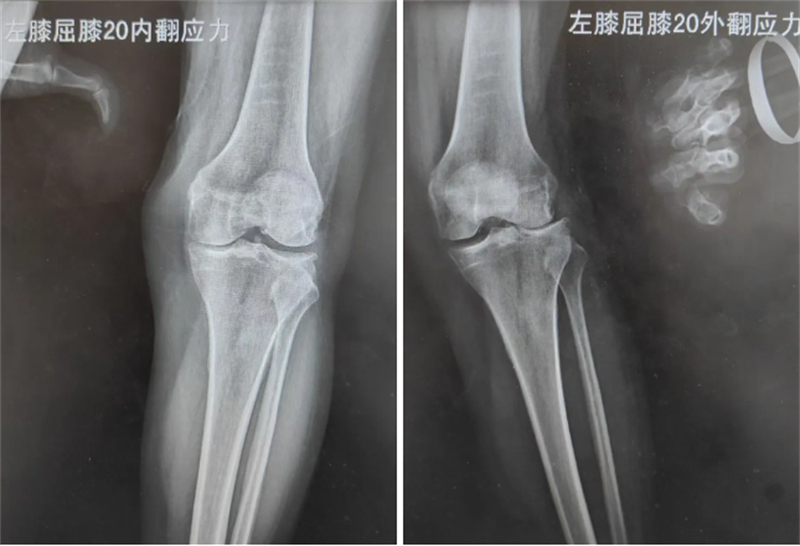

膝关节骨性关节炎是老年人膝关节疼痛的一大病因,困扰无数老年患者,59岁的徐女士就一直被该病困扰,出现膝关节疼痛、行走困难的情况。通过X线及磁共振检查,医生发现徐女士为膝关节外侧盘状半月板撕裂后局部常年受应力刺激,关节外侧软骨磨损所致的膝关节外侧间室骨性关节炎。考虑徐女士膝关节的韧带及内侧间室软骨完好,仅为膝关节外侧间室的软骨磨损,科室决定实施膝关节外侧单髁关节置换术,在解决徐女士膝关节疼痛的基础上,尽可能减少正常膝关节结构的损伤,实现术后快速康复、减少疼痛的目的。

医生介绍,徐女士的这场手术,能否精确完成术前设计,恢复膝关节正常的关节线高度和下肢的力线是手术的重点。术前在手术机器人智能系统上根据患者下肢的CT测量数据进行一系列的3D建模、数据分析、术前计算、术中计划,最终确定假体的大小、截骨范围、放置位置等。